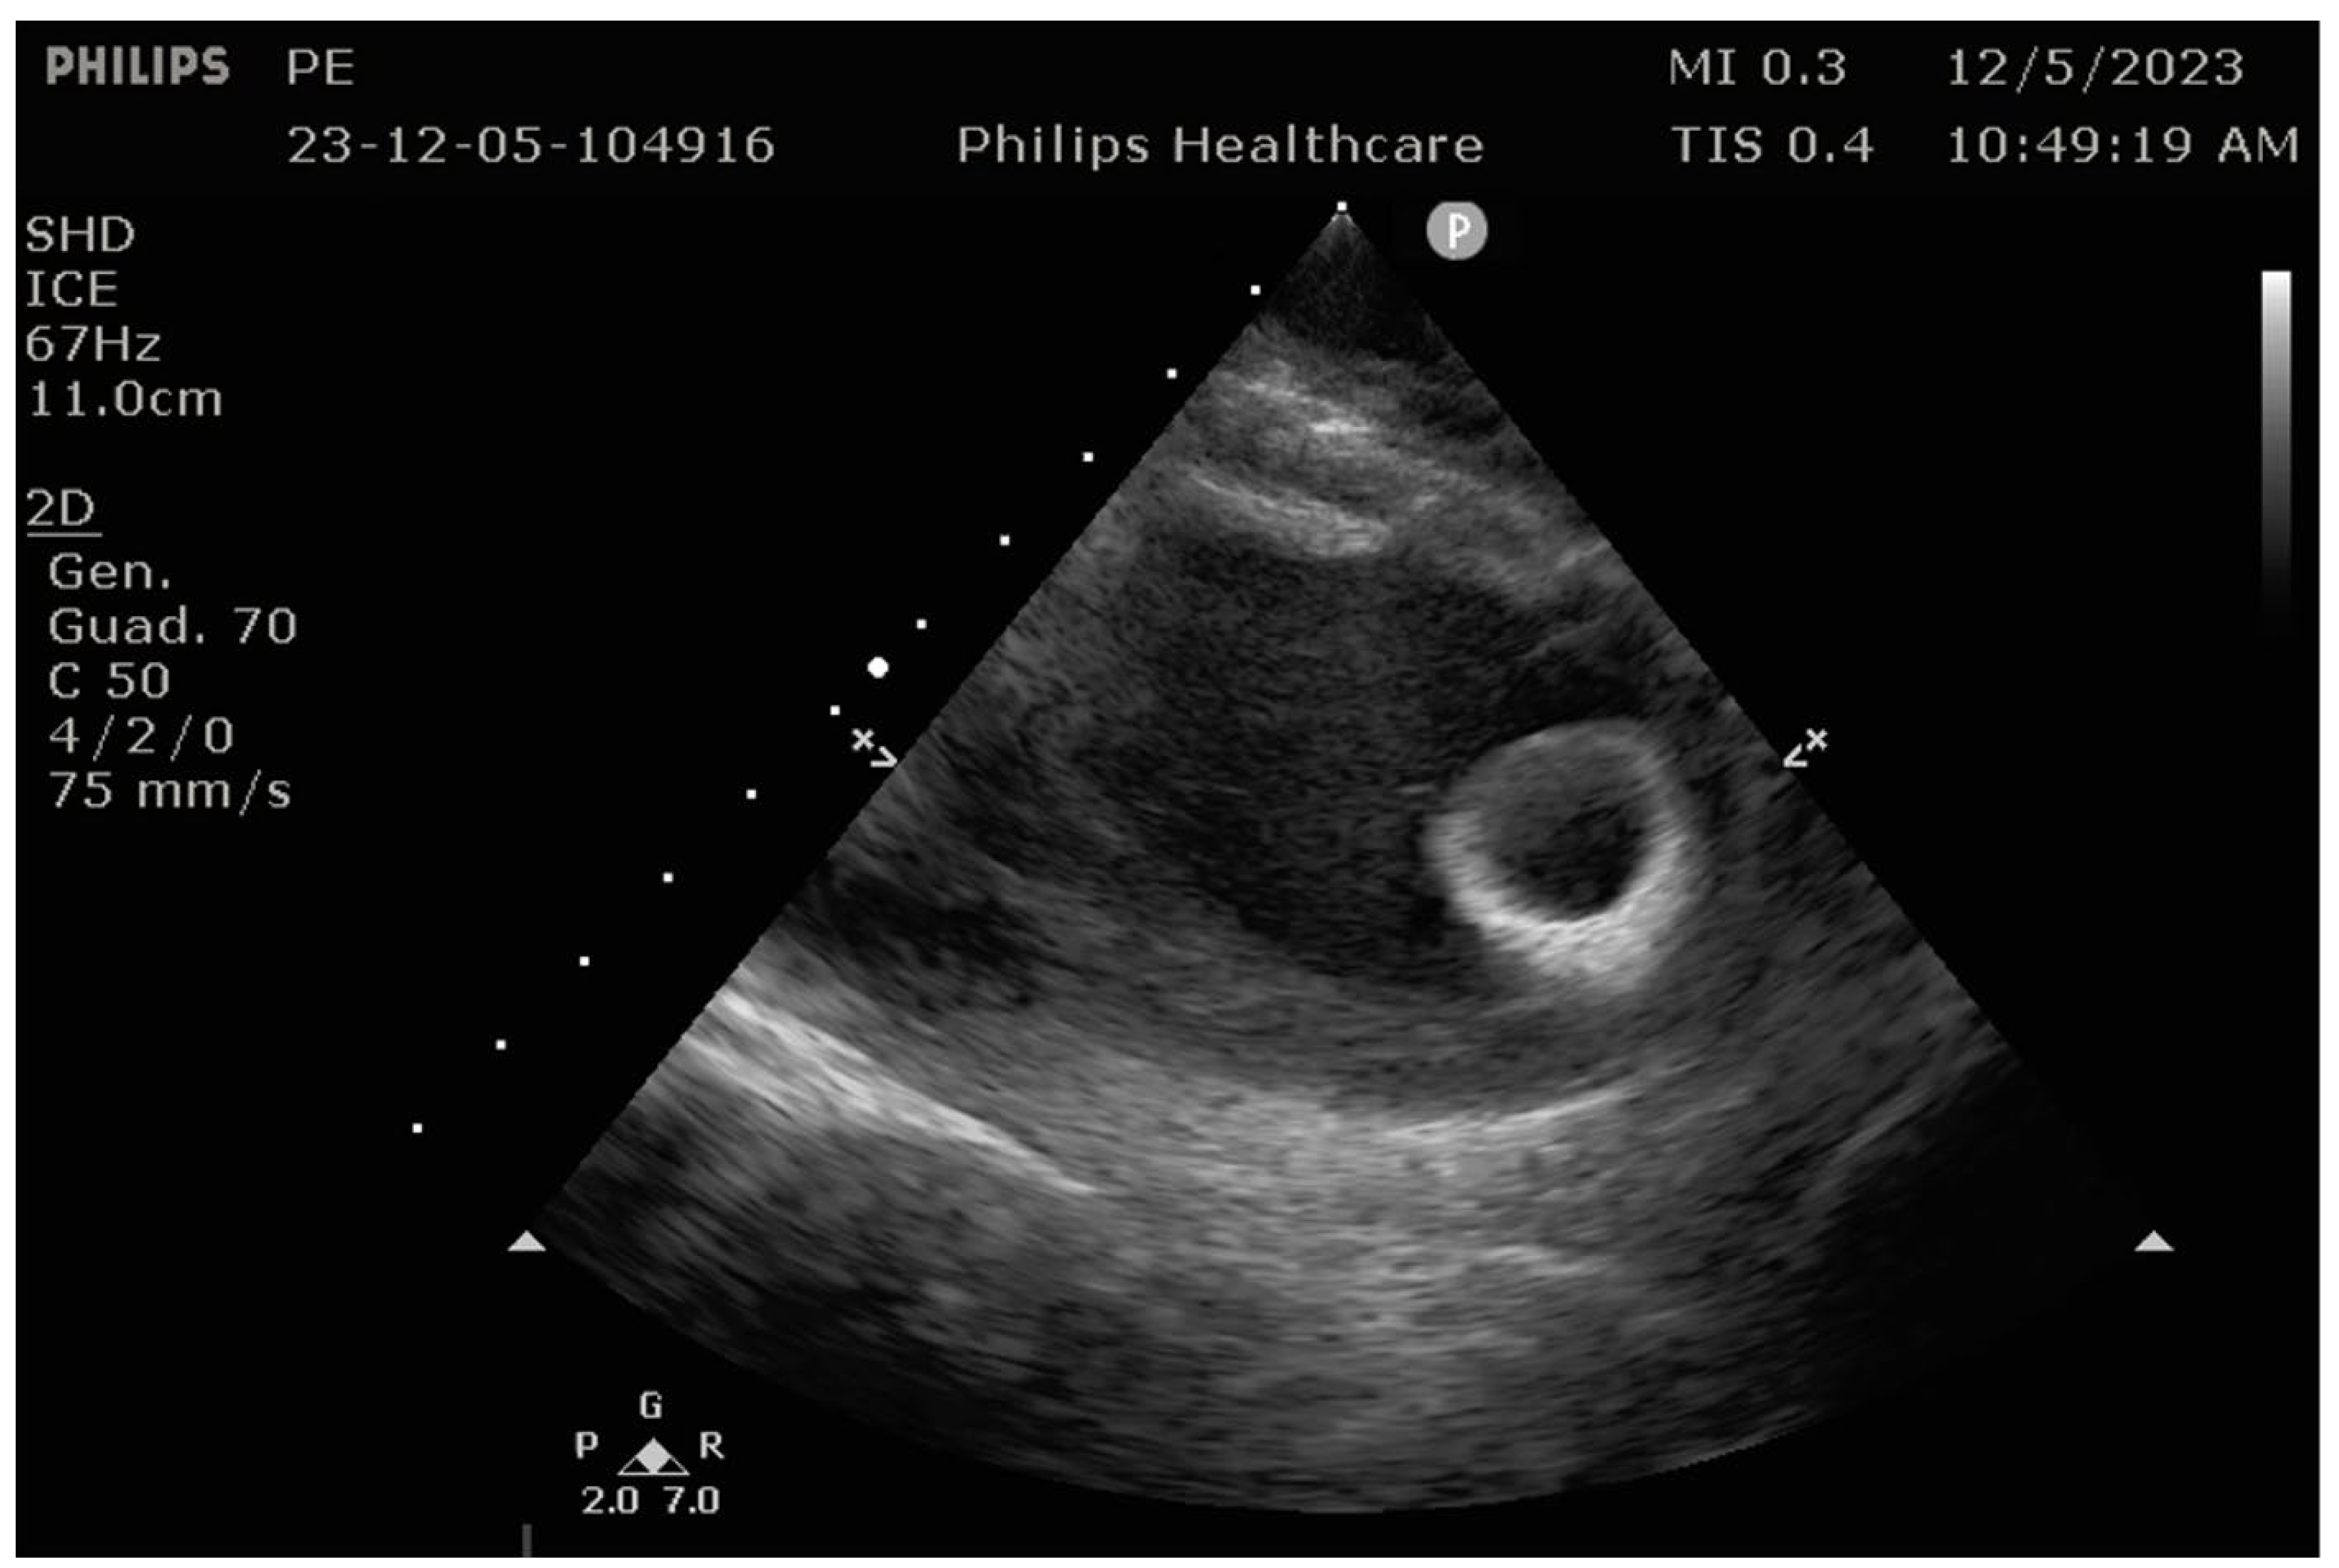

7.5. Intraprocedural Considerations